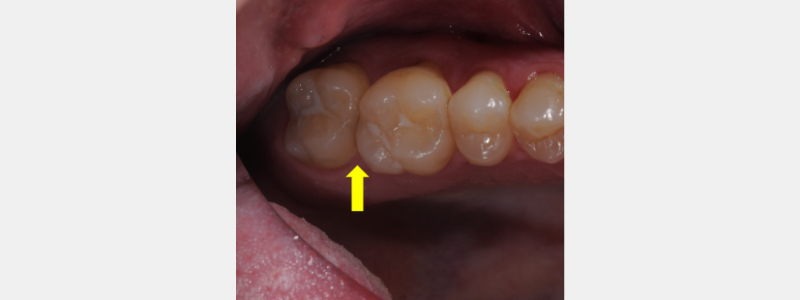

I will use a clinical example to describe and outline the technique for closing interproximal spaces. My patient, Matt, scheduled an appointment to evaluate an open proximal contact of his second maxillary molar. (Fig. 1)

He complained of food trapping, gingival irritation, and bleeding. Matt has a history of clenching but does not wear a protective occlusal splint. At age 40, he has had no dental restorations and is caries-free. As a regular flosser and a consistent dental re-care patient, this situation was frustrating and irritating to him. He asked for a solution to this concerning problem.